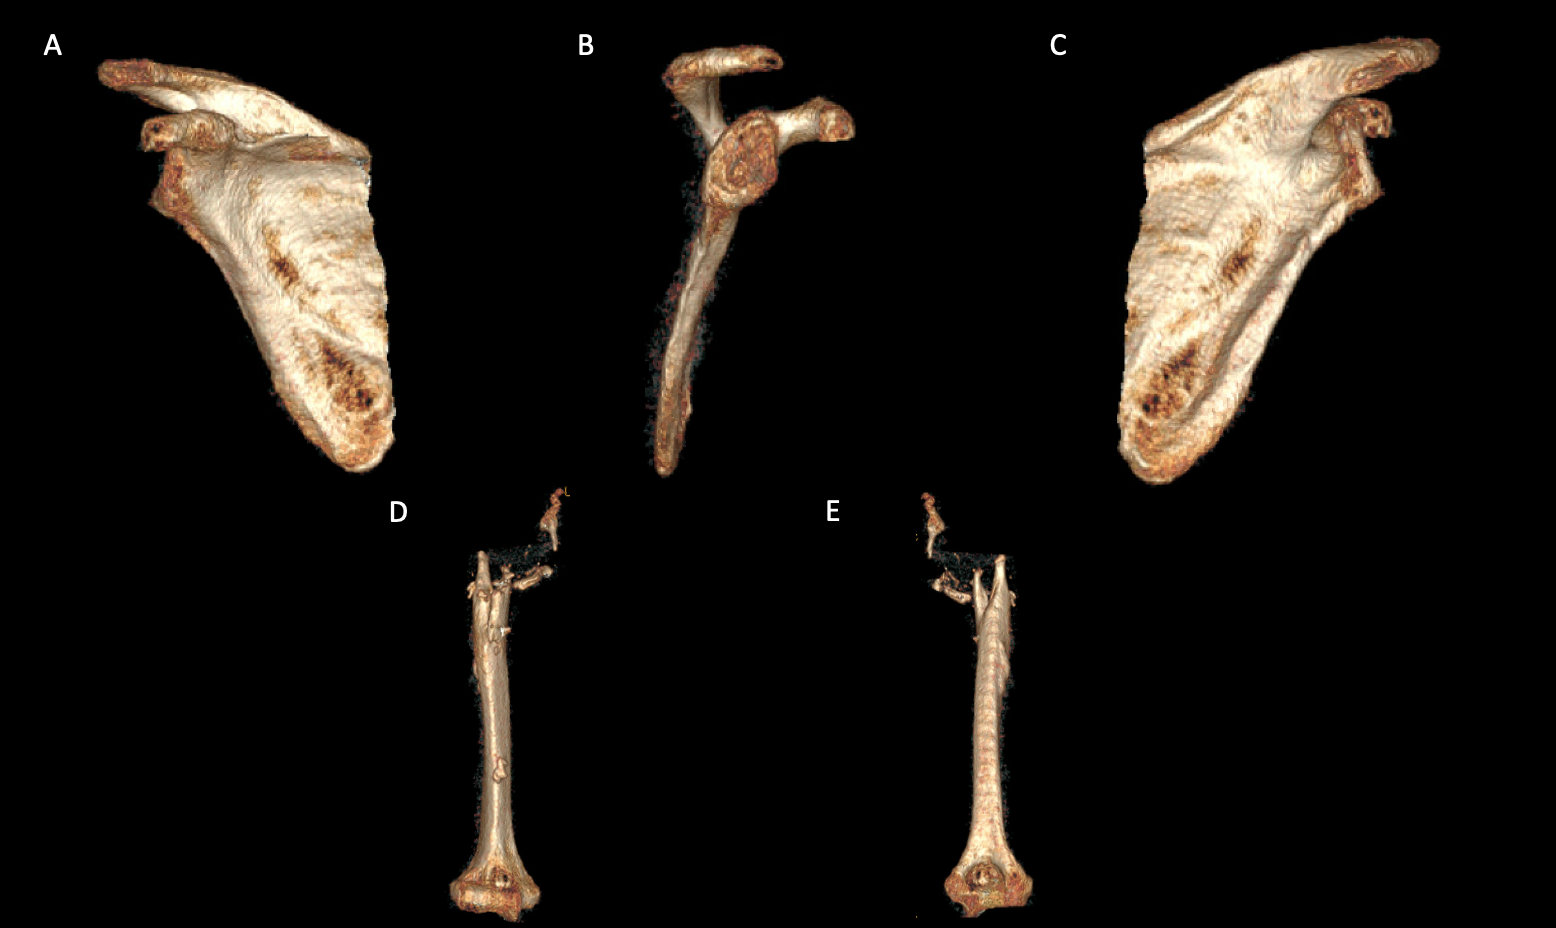

A 69-year-old woman presented after resection arthroplasty of her right shoulder hemiarthroplasty and completion of antibiotic treatment for culture negative PJI for evaluation of reconstructive options. She had a history of a displaced two-part right proximal humeral fracture which was repaired with an intramedullary nail. Post operatively, she had persistent pain and CT scan of the shoulder showed two screws in the humeral head that extended through the cortex and into the glenohumeral joint. The screws were removed and replaced with smaller screws. Subsequently, she had non-union of the fracture in the setting of deltoid weakness and was revised to a right hemiarthroplasty (Figures 1-3). Post operatively, she had persistent pain refractory to physical therapy and diminished function that was impacting her quality of life. She sought subsequent care, and there was concern for arthroplasty failure secondary to a septic versus aseptic condition and the decision to proceed with resection arthroplasty was made. During resection arthroplasty, a significant amount of fluid was expressed from the joint space. The combination of the clinical picture of progressive and persistent pain and the gross expression of fluid were concerning for PJI and the decision to treat was made. It was felt that the extent of humeral bone loss did not allow for a stable cement spacer, so none was placed. Intraoperative joint fluid cultures, anaerobic, and fungal cultures were all negative for growth. Cultures were held for 21 days to rule out C. Acnes infection. Considering the plan for future reimplantation, infectious disease consultation recommended a 6-week course of vancomycin but after 2 days the patient had a transfusion reaction and was switched to daptomycin. She was left with markedly limited active motion associated with severe pain. After completion of the antibiotic course, the patient elected to proceed with revision surgery. This patient had a flattened and distorted glenoid and atrophied rotator cuff musculature demonstrated prior to resection arthroplasty on CT (Figure 4). This patient’s prior hemiarthroplasty had been a tantalum coated, cemented humeral stem with associated marked thinning of the humeral cortex even prior to resection arthroplasty, and this resulted in a large amount of proximal humeral bone loss during the resection (Figure 5). The patient was severely debilitated by the right shoulder and wanted to proceed with reconstruction. Because of the combination of glenoid and humeral bone loss and the lack of rotator cuff attachments, a custom constrained prosthesis design process was initiated, and the implant was available 16 months after the resection arthroplasty. Preoperative 3 phase SPECT (Single Photon Emission Computed Tomography) three phase bone scan, upper extremity CT, and blood work (WBC 5.4, ESR 9, CRP 0.8) showed no suggestion of active infection.